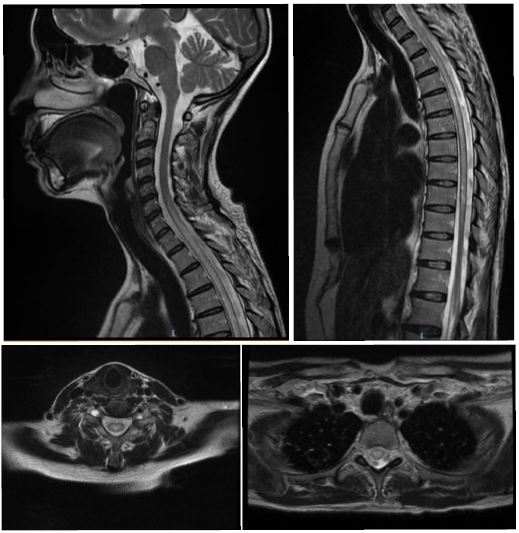

La tomografía abdominal sin contraste mostró una tumoración sólida de probable origen neoformativo en espacio pararrenal anterior izquierdo (retroperitoneo) parcialmente valorada por falta de la fase contrastada, asociada a adenopatías retroperitoneales ipsilaterales (figura 1). La resonancia magnética nuclear (RMN) mostró alteración de la señal en la medula espinal de la región cervical y dorsal de C5 a T10, luego de la administración de contraste se observa áreas de realce en esas regiones. Los cuerpos vertebrales sin evidencia de lesiones expansivas ni colapsos (figura 2). Además, la RMN encefálica evidenció lesiones desmielinizantes en la región posterior del tronco del cuerpo calloso, en la región posterior de los cíngulos a predominio izquierdo y en la región posterior al cuerno occipital del ventrículo lateral izquierdo (figura 3).

Esta paciente tiene una historia clínica caracterizada por dos síntomas cardinales: dolor abdominal y paraparesia. El dolor abdominal es transitorio pero la paraparesia es progresiva y se convierte en el principal problema para la paciente. Cuando se presenta un problema neurológico lo primero es delimitar su topografía y luego documentarla con una imagen si es apropiado. Luego de eso a partir de los hallazgos en las imágenes y la historia clínica plantear las principales posibilidades diagnósticas. Los síntomas y signos neurológicos en esta paciente como la paraparesia, la hiperreflexia, signo de Babinski bilateral, compromiso de esfínteres y nivel sensitivo, identifican claramente una lesión en médula espinal, es decir un síndrome medular. Esta lesión puede ser intrínseca como una mielitis transversa o extrínseca a la medula como una lesión vertebral y compresión de ésta. La mejor imagen para caracterizar un síndrome medular es una RMN contrastada. Esta se solicita de acuerdo con el nivel sensitivo encontrado y con visualización adicional de los demás segmentos pues las lesiones pueden ser multifocales. En la paciente la RMN de médula espinal muestra una extensa lesión hiperintensa en secuencia T2 que capta contraste desde C5 a T10. Que sea hiperintensa en T2 y se realce con contraste es compatible con una lesión inflamatoria. Una lesión medular inflamatoria no compresiva subaguda como ésta es compatible con una mielitis transversa (MT). Cuando una lesión medular inflamatoria tiene una extensión de tres o más segmentos contiguos se denomina mielitis transversa longitudinalmente extensa (MTLE), en contraposición a la mielitis transversa más común de una menor longitud. La MTLE es una clave importante para hacer más específico nuestro diagnóstico diferencial (1) (tabla 1).

Nuestra paciente, mujer de 49 años, presenta un cuadro subagudo de dolor abdominal y paraparesia inicialmente asimétrica. La paraparesia progresa, encontrándose hallazgos clínicos de primera neurona motora (paraparesia espástica), compromiso autonómico (globo vesical y estreñimiento) y nivel sensitivo en D5, diagnosticándose clínicamente un síndrome medular. La RMN medular muestra una lesión intramedular cérvico dorsal (C5-T10), con captación de contraste, compatible con una MTLE. La RMN cerebral confirma la presencia de múltiples lesiones periventriculares (cuerpo calloso, ventrículo izquierdo) sin captación de contraste. Ambas lesiones (medulares y cerebrales), compatibles con enfermedad desmielinizante. El estudio de LCR fue normal. Se encontró una masa abdominal (adenopatía) compatible con un Linfoma de Hodgkin clásico en anatomía patológica.

En nuestra paciente se encontraron lesiones tipo MTLE y lesiones en sustancia blanca periventriculares en los estudios de RMN con contraste. Las lesiones medulares fueron de preferencia centrales con captación de contraste. Las lesiones encefálicas no captaron contraste. Los reportes en la literatura no son diferentes a nuestros hallazgos.